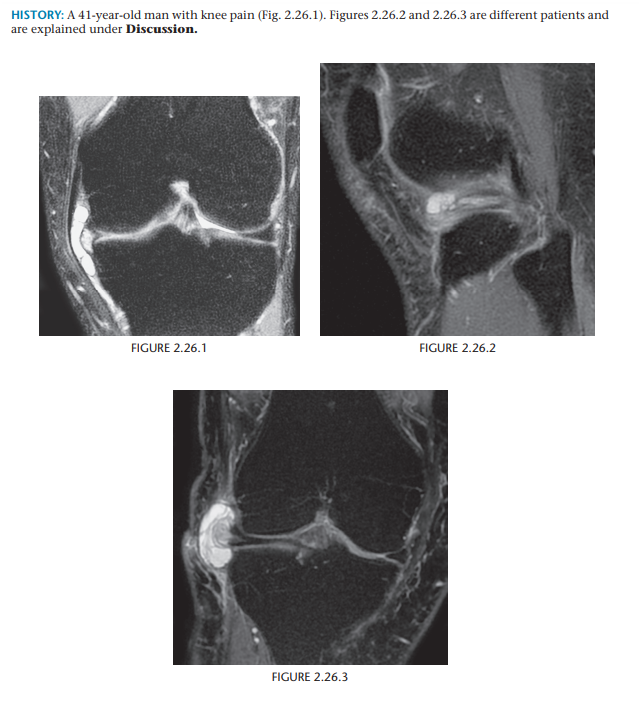

Osteochondritis dissecans (osteochondrosis) of the medial femoral condyle

An osteochondral fracture that was initially caused by shearing, rotatory, or

tangentially aligned impaction forces

semicircular lucency, with an adjacent bony fragment,

on the lateral aspect of the medial femoral condyle

(arrows)

Encircling fluid or focal cystic areas between the medullary canal and the fragment on MRI suggests a potentially loose or unstable fragment.